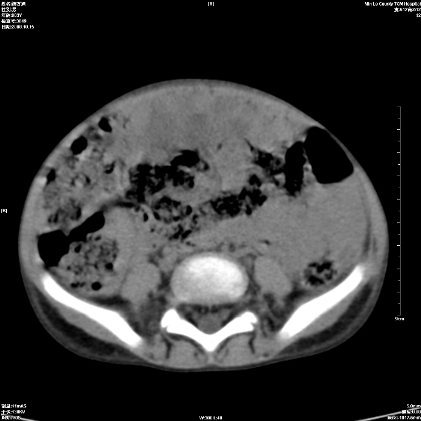

标题: PED1609:男性,3岁。彩超示肝Ca.

3岁;肝低密度灶;有钙化;有转移灶;考虑肝母细胞瘤;查afp

考虑神经母细胞瘤并肝转移

考虑:1、右侧后下纵隔畸胎瘤。

2、肝脏多发血管内皮细胞瘤。

建议:增强确诊。